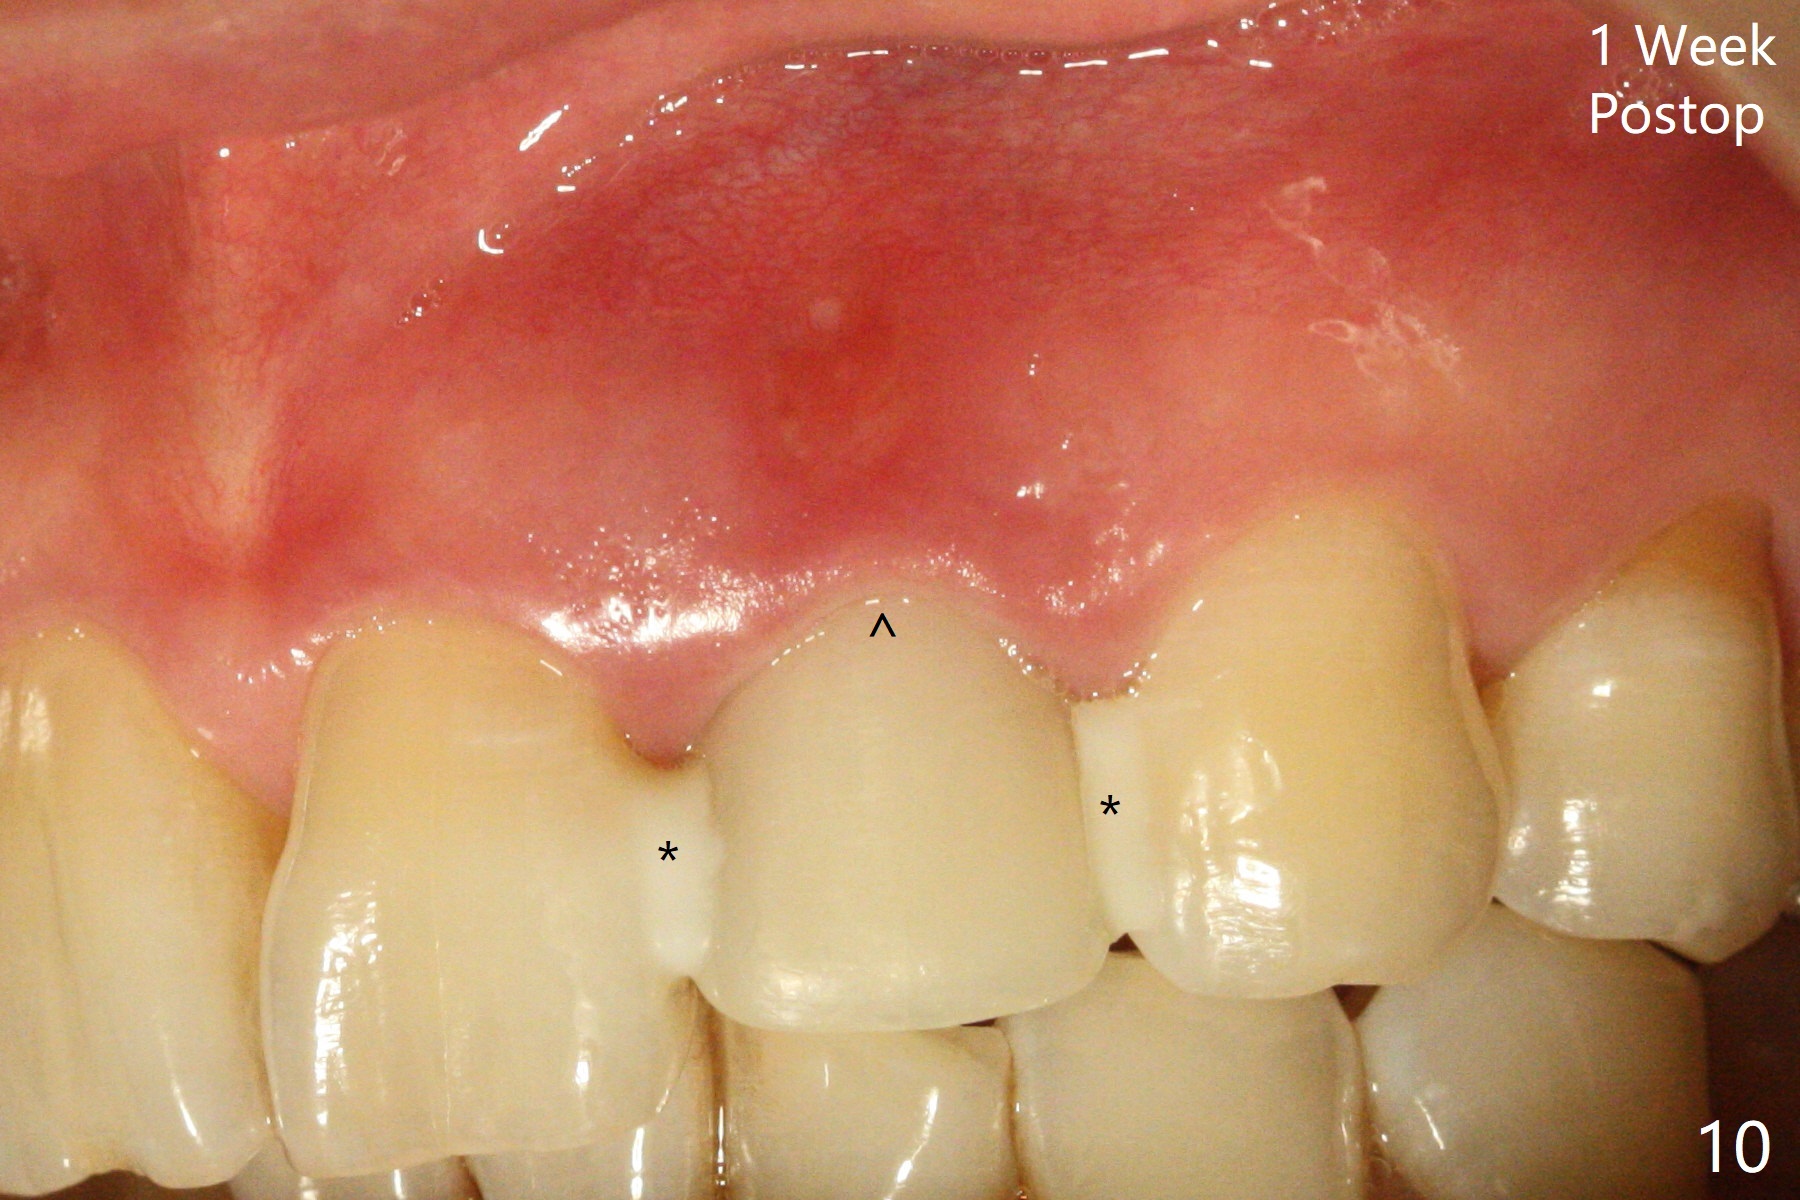

病人回来带来瘘道(图一),不过不会增加难度,病牙去除,它便自动消失。尽管颊侧骨壁完全失去,颊侧牙龈仍丰满(图二),为什么呢?第一,因为粗大牙根存在,第二两旁牙齿,牙槽骨撑着帐篷(侧切牙颊侧牙龈),第三,牙冠。为了防止术后牙龈塌陷,尽量不切开,即刻放置植体(牙根);由于前牙缘故,这次植体不能很大,所以植骨必须过度(over grafting),最后即刻制作临时牙冠,撑住牙龈。这就是所谓每个人进入角色。这个牙根有一种先天性畸形:dens in dent (图三(腭侧观):箭头)。尽管腭侧牙根畸形,腭侧骨壁吸收临床上并不严重,所以钻洞仍偏腭侧。当预定最后钻头还在钻洞时,填入大量粘性骨块(图四:*),细长植体还没有完全卡入鼻底(图五),最后好像可以(图六,七)。植体,骨粉入位(图八),最后临时牙冠出场(图九)。尽管植体小,术后一周临时牙冠仍然可以维持牙龈原有形状(emergency profile,图十:箭头(*:树脂强化牙冠固定))。图十一以不同角度显示瘘道缩小。术后三周取出有些松动的临时牙冠,骨粉虽然还没有被肉芽组织整合,但是显得正常,周围牙龈健康(图十二)。术后4个月牙龈形态正常(图十三),没有触痛;颊侧骨板轻度凹陷(图十四);骨粉仍在原位(图十五)。术后7个月骨粉仍在原位(图十五,十六,但是冠部密度减低(可能骨粉流失,需要牙周或者树脂敷料保护)),没有螺纹暴露。但是牙冠边缘暴露,说明牙龈收缩(图十七,与图十三对比),颊侧骨板仍塌陷(图十八)。插入龈线取得多个目的:修整基台边缘,取模,颊侧牙龈推向颊侧,有利于即将衬里牙冠龈缘进入龈下(图十九)。取模后牙冠边缘(图二十:<)衬里,然后修整,变窄,以便插入龈下,促进颊侧牙龈下降(图二十一,二十二)。术后8个月牙冠粘固前牙龈健康(图二十七,八),牙冠(图二十九)固位后,病人满意(图三十),咬合调整(图三十一),注意腭侧粘固粉流出通道(<)。